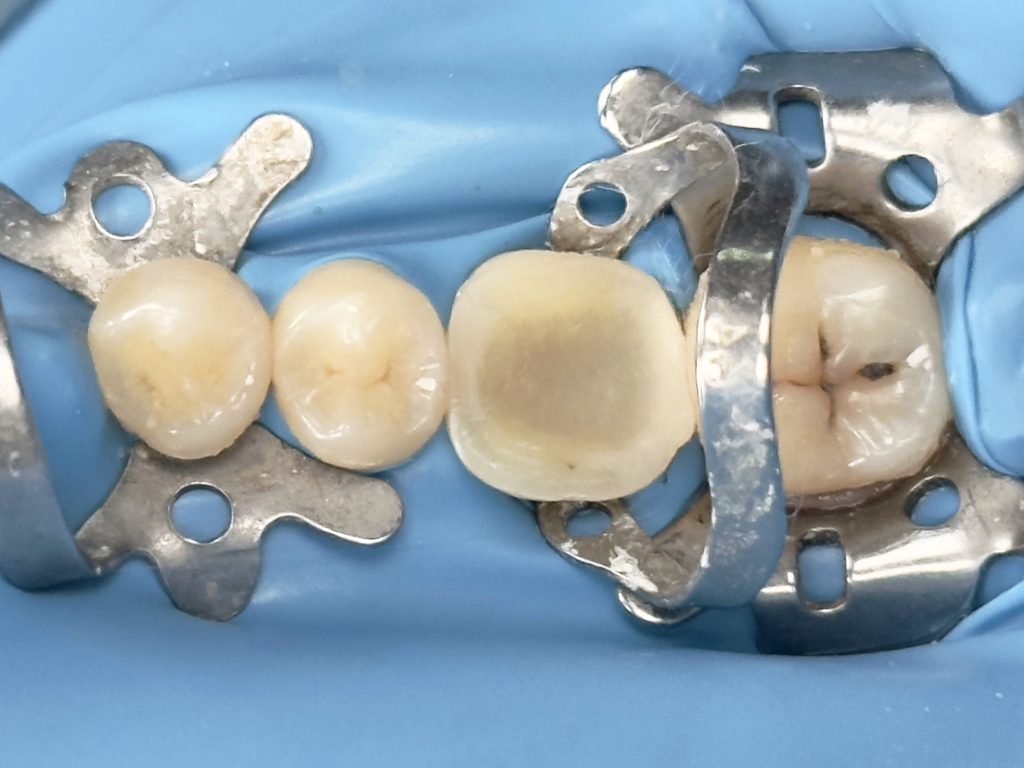

3rd visit :-

-Air abrasion of both tooth & restoration

-Cementation of the home made indirect composite

-Finishing &polishing